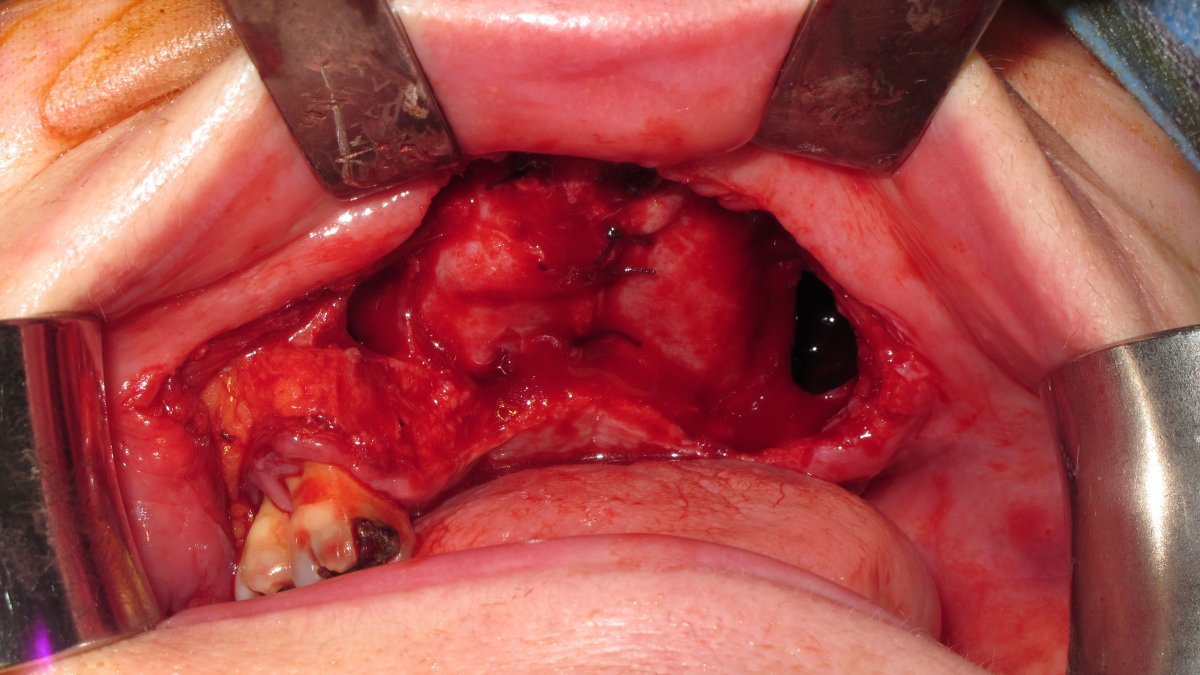

post-resection